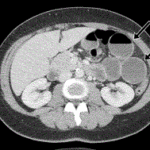

The diagnosis of internal hernias is a nightmare. However, these authors make your task more simple based on ten different signs. You will not miss any in the future! Article: Diagnosing internal herniation after laparoscopic Roux-en-Y gastric bypass: usefulness of...